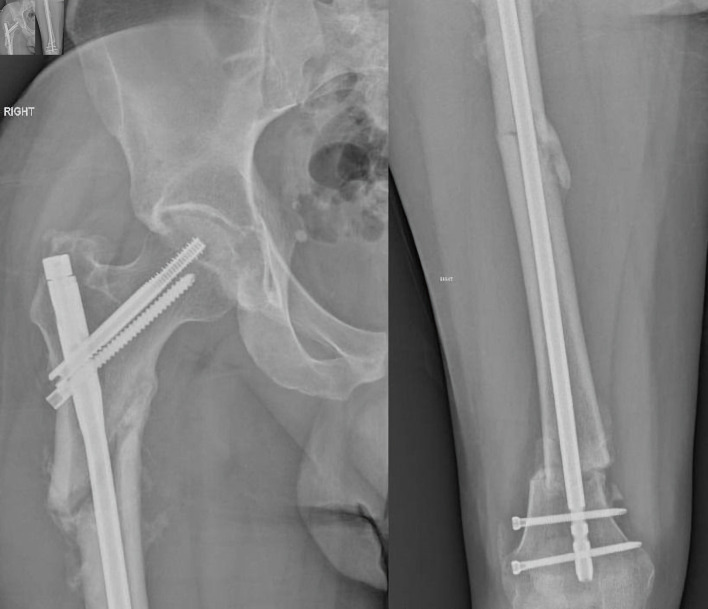

Femoral fractures are indubitably common injuries that can occur either from high-energy trauma in young patients or due to fragility in the geriatric population. Femoral fractures affecting two or more regions of the femur are exceedingly infrequent injuries, ordinarily caused by high-energy trauma and are considered segmental femoral fractures. We present a rare case of a 33-year-old male patient presented to our Emergency Department with multiple femoral fractures at the subtrochanteric, diaphyseal and supracondylar femoral regions, a condition regarded as double segmental femoral fracture. After assiduous consideration of treatment options, intramedullary nailing was employed for osteosynthesis. Fracture reduction was laborious, as an entirely separated femoral fragment was present between the fracture lines. The reaming process required paramount attentiveness as the middle femoral fragment was prone to rotational displacement by the reamer. Finally, the intramedullary nail was successfully placed, and the patient was discharged without complications after 11 days of hospitalization. Currently, the patient is capable of full weight-bearing without crutches. This paper underlines the challenges that double-segmental femoral fractures' treatment can bring on to the orthopedic surgeon.

Abstract Image